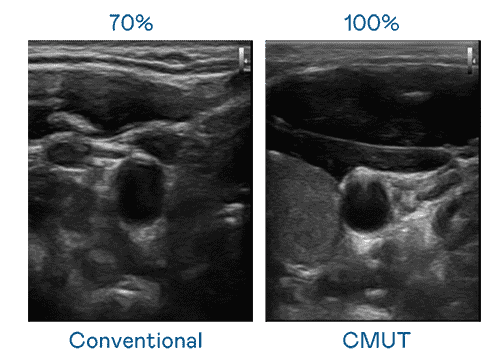

CMUT 技术是一种用电容式微机电元件来产生超音波讯号的技术。。与传统 PZT 压电式技术相比,,CMUT 频宽增加 30%,,,,更宽频的超音波讯号让影像解析度大幅提升,,是实现高影像品质医疗超音波扫描、、促进精准医疗发展的关键技术。。。

大频宽带来超清晰影像

超音波影像的解析度高低,,,,首先取决于探头能发出的讯号频宽。。。汇旺支付 CMUT 可提供高清晰的超音波讯号,,提供高频宽、、、、高灵敏度、、、影像纹理细节更高的超音波影像,,,,协助医护人员缩短影像判读时间及利用精准的医疗影像进行诊断。。